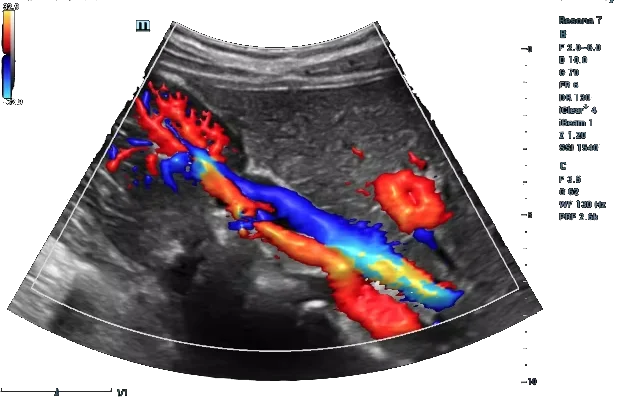

Precision Blood Flow and Vascular Imaging for Early Detection of Circulatory Issues

Our advanced Doppler studies assess blood flow and vascular health, detecting circulation issues early for conditions related to arteries, veins, and organs, ensuring accurate diagnosis and effective treatment planning.

Color Doppler Studies

Color Doppler studies evaluate blood flow in veins and arteries, helping detect abnormalities like blockages, clots, or vascular conditions. This non-invasive imaging technique is especially valuable in monitoring fetal development and maternal health during pregnancy, ensuring proper circulation and identifying any risks early for prompt medical intervention.